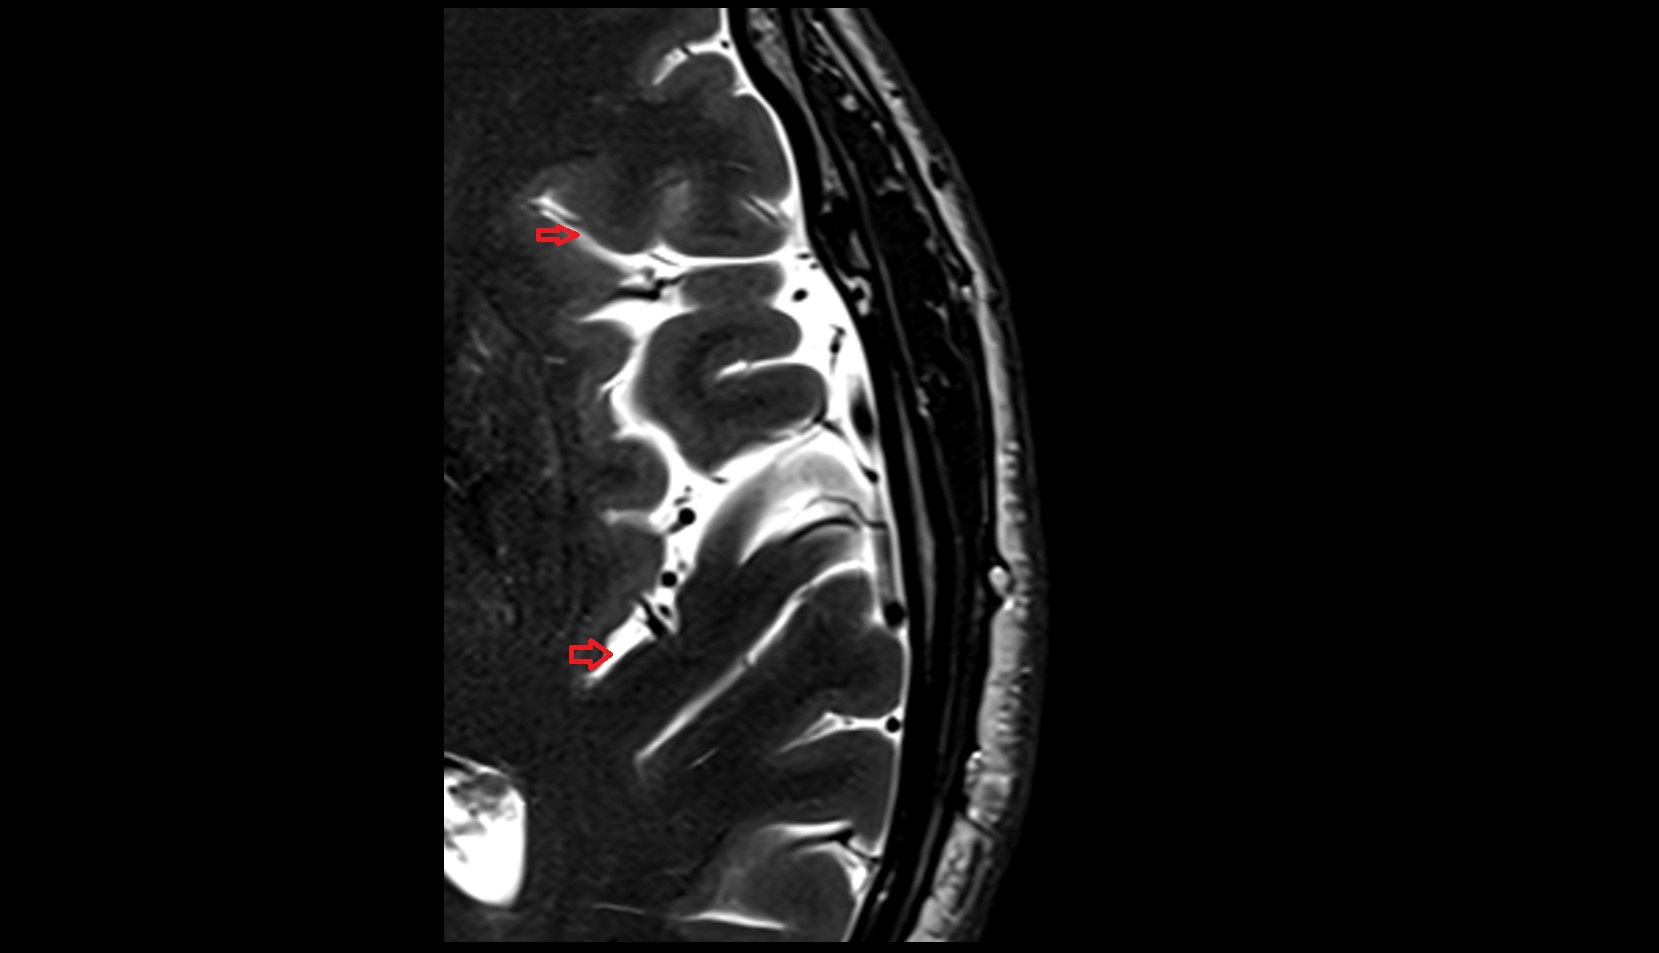

- Uterus

- Body of uterus

- Fundus of uterus

- Cervix of uterus

- Isthmus of uterus

- Vagina

- Fornix of the vagina

- Endometrium of uterus

- Myometrium of uterus

- Perimetrium of uterus

- Junctional zone of uterus